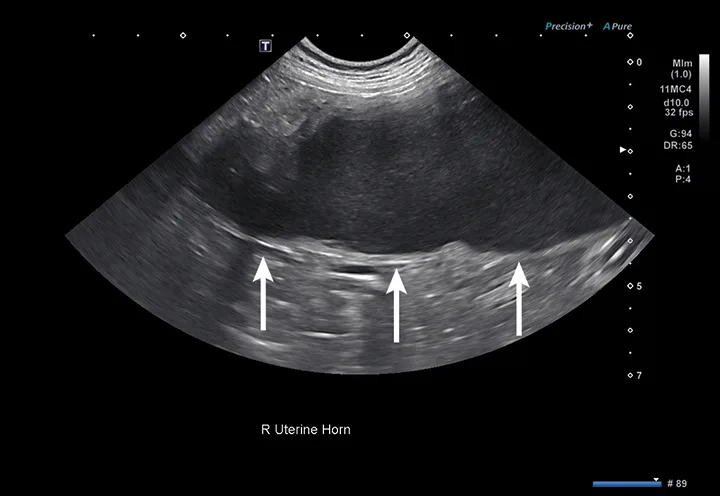

4. Female Reproductive Evaluation (Pyometra, Dystocia)

The uterus normally appears as a tubular structure between the urinary bladder and colon on ultrasound. In dogs, the uterus can have different thicknesses and echogenicity depending on the stage of the estrus cycle; however, in cats, the uterus is usually not visualized.15 Because uterine horns have small wall thickness, they can lack easily identifiable wall layers, which can be used to help distinguish a uterine horn from a nearby intestinal segment with thicker and more apparent wall layers. (Figure 4).15

Ultrasound image of an enlarged uterine horn containing hypoechoic fluid in a dog and arrows pointing to the uterine wall.

FIGURE 4

Right uterine horn of a dog with pyometra. The uterine wall (arrows) is too thin to be a normal small intestinal segment.

Pyometra is a reproductive emergency that requires rapid diagnosis and treatment.16 In patients with pyometra, the uterus contains variable amounts of echogenic intraluminal fluid, with varying degrees of dilation and wall thickness.16 Ultrasound findings should be considered in conjunction with patient history, physical examination findings, and laboratory results, as other less common differentials (including mucometra, hydrometra, and hemometra) are also possible.16 Distinct wall layering may be lost in small intestinal segments that are severely dilated; this can be similar in appearance to a fluid-dilated uterus.